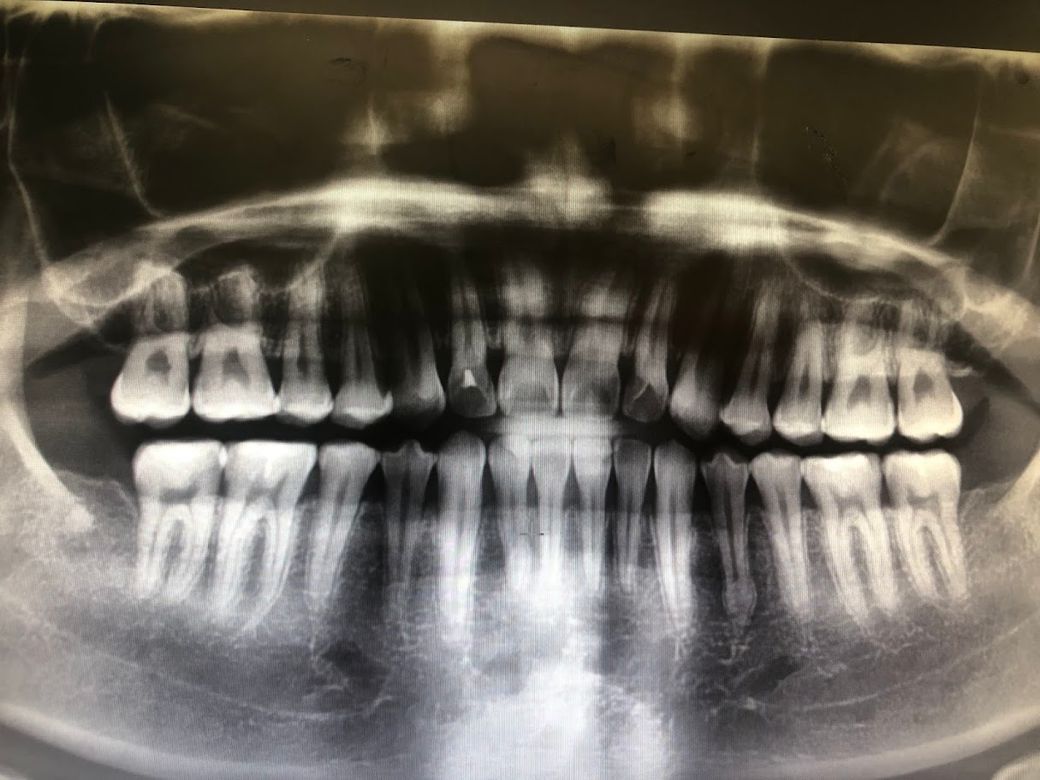

제 치아 엑스레이 상태가 궁금합니다.

현재 26살 입니다

치간칫솔을 사용중인데 또래 20대에 비해서 잇몸이 너무 내려간거 같아요

치아들에 ss, m 사이즈가 그냥 쑥쑥 들어가요

그리고 치아들 상태도 확인하고 싶어요

• 1번 째 사진

x-ray 사진에서 잇몸뼈(치조골) 상태는 정상인 것으로 보입니다. 치간 치솔이 들어가는 것은 본인 치간치솔을 잘 사용해서 일 수도 있습니다. 잇몸 상태는 구강검사 하여 육안으로 보아야 합니다.

2. 잇몸뼈가 아주 많이 퇴축되진 않았습니다

3. 어금니 부위 마모가 어느정도 진행되었습니다이갈이나 이악물기 습관이 있다면 고치시기 바랍니다